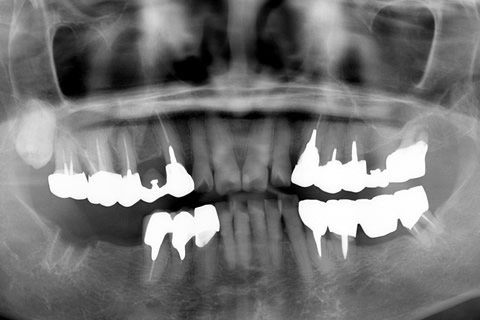

• 症例2

治療前

インプラント埋入時

治療後

年齢・性別

57歳男性

治療期間

3ヶ月

抜歯

なし

治療費

154万円

備考

左上5.6.7 及び左下6.7欠損

治療内容

左上5.6.7と左下6.7欠損部にインプラント埋入

施術の副作用(リスク)

オペによる知覚障害。インプラントによる歯肉炎。インプラント脱落。